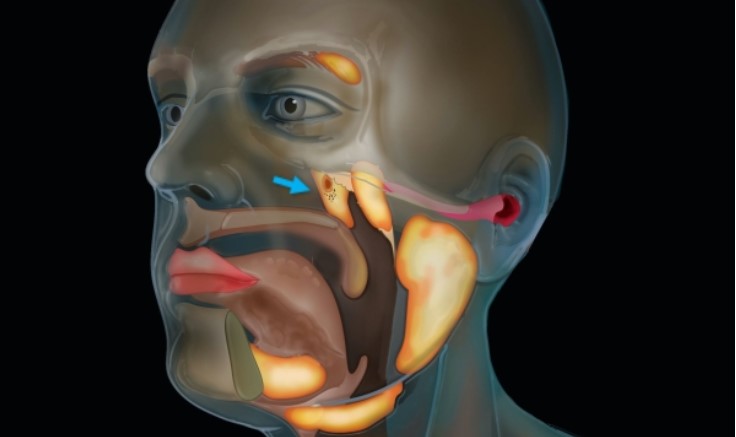

Vedci len čírou náhodou objavili v ľudskej hlave úplne nový orgán

Vedci neustále objavujú nové veci a jedným z ich posledných objavov je totálne prekvapivo nový orgán v ľudskej hlave. Tento nový nález holandských vedcov mimoriadne prekvapil, pretože ho objavili vtedy, keď študovali rakovinu prostaty.

Pri skúmaní CT a PET snímok si vedci v Holandskom onkologickom ústave všimli nový súbor predtým neidentifikovaných orgánov. Ide o skupinu veľkých slinných žliaz (nazývaných tubárne slinné žľazy), ktoré sa nachádzajú za nosom, presnejšie v mieste, kde sa nosová dutina stretáva s hrdlom. Ale aký je ich účel? Zdá sa, že tieto žľazy sú tam zrejme na to, aby mazali a zvlhčovali oblasť hrdla za nosom a ústami. Objavenie žliaz bolo pre mnohých vedcov šokom, keďže až do dnešných dní dlho zostali žľazy bez povšimnutia.

Dr. Wouter Vogel, radiačný onkológ z Holandského onkologického ústavu, sa vyjadril takto: „Ľudia majú tri skupiny veľkých slinných žliaz, ale nevedeli sme, že sa nachádzajú aj tam. Doteraz sme vedeli len to, že jediné slinné alebo slizničné žľazy v nazofaryngu sú mikroskopicky malé a všetky z nich sú rovnomerne rozložené po celej sliznici. Predstavte si teda naše prekvapenie, keď sme ich našli.“ Aj keď tím vedcov chce viac skúmať iluzívne žľazy, je zjavne dosť ťažké sa k nim dostať. Doktor vysvetlil: „Ich poloha nie je príliš prístupná a na jej zistenie potrebujete veľmi citlivé snímky.“

Doktor zároveň dodal, že objavenie týchto žliaz by mohlo vysvetliť fakt, prečo mnoho ľudí, ktorí podstúpia rádioterapiu hlavy, často trpia problémami so suchom v ústach a majú tiež problémy s prehĺtaním. Verí sa, že jediný nesprávny zásah rádioterapie môže natrvalo poškodiť jemné tkanivá, pretože sa ich nikdy nikto nepokúsil ušetriť. Vedci teraz dúfajú, že tento objav pomôže pacientom s rakovinou prekonať niektoré ich komplikácie po rádioterapii, pretože sú presvedčení, že veľa komplikácií súvisí s objavenými slinnými žľazami.